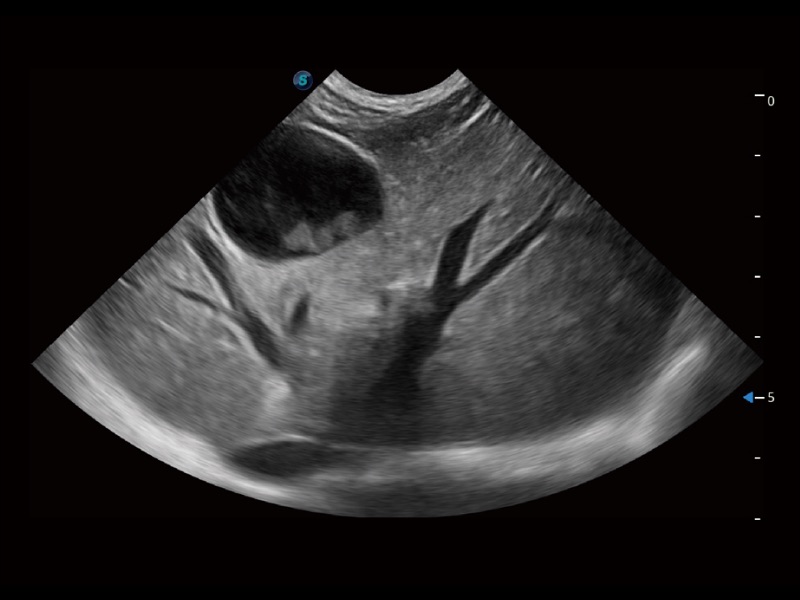

优异的基础图像

(犬)四腔心

(犬)四腔心MQA